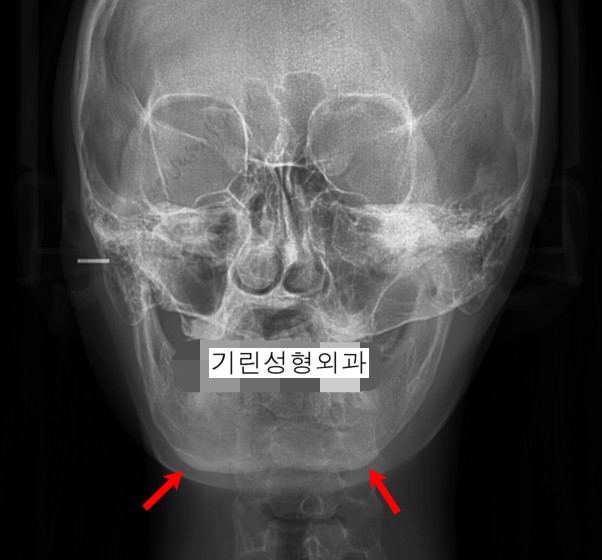

-이차각 및 정면효과 미비-

-일반 긴곡선턱축소 후 이차각 및 비대칭, 정면효과미비 엑스레이-

긴곡선절제는 과거 시행되던 사각턱축소(귀밑각만의 제거)에서 보완된 수술방법이지만 다양한 턱 모양에 적용시키기에 완벽한 수술방법이라 할 수는 없습니다. 긴곡선으로 절제하는 범위가 어디까지인지, 얼마만큼인지, 어떻게 절제하느냐에 따라 효과가 달라지기 때문입니다.

일반 긴곡선절제술은 위 사례처럼 정면효과가 없거나 비대칭이 생길 우려가 있기 때문에 턱중앙(앞턱축소)까지 절골하는 섬세한 기술을 요합니다. 타원에서 상담을 받고 오신 환자분께서 '턱끝까지 자르면 신경선이 다친다더라' '위험해서 턱끝까지 못 자르기 때문에 티절골을 하는거라더라' 라는 말씀을 듣고오셔서 질문하는 경우가 있습니다. 과거 수술방법대로 직선절골을 하게되면 신경손상의 염려가 있지만 수술방법을 안전하게 보완하였기 때문에 안심하고 수술받으셔도 됩니다.